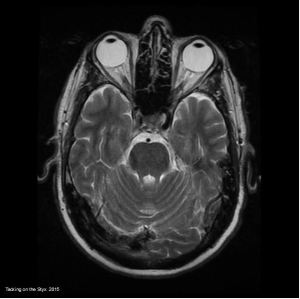

If you are looking for free-use brain scan imagery (with citation) click to the MRI page for a comprehensive image collection of an adult male. Additionally, there is now a set for the spine complete with scoliosis.